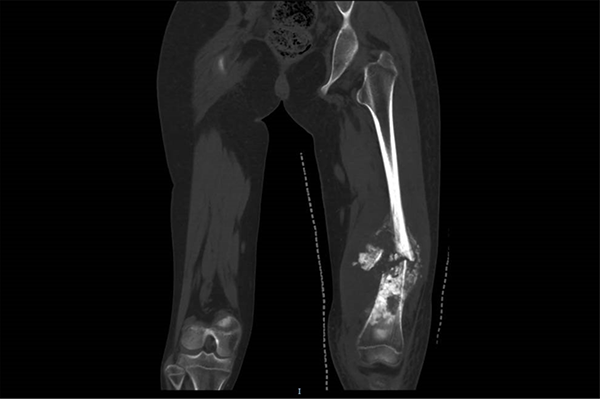

这是小鱼的术前CT影像

针对小鱼的病情——股骨下段肿瘤长达15厘米、宽度达6.5厘米,王克及其团队制定了“新辅助化疗+保肢手术”的个体化方案。经过4个月8次高强度化疗,患儿肿瘤宽度从6.5厘米缩小至3.5厘米,腿围由38厘米降至33厘米,为后续保肢手术创造了关键条件。